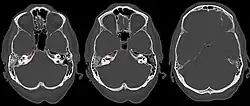

| Apicitis petrosa as seen in computed tomography | |

In persons with longstanding ear infection and typical symptoms, medical imaging such as CT or MRI of the head may show changes that confirm disease involvement of the petrous apex of temporal bone.